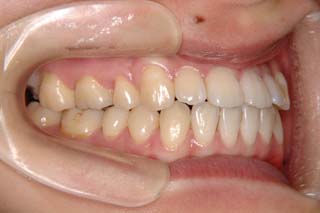

外科症例(アゴの輪郭でお悩みの方) 下顎前突

装置撤去です。動的処置は2年弱でしたので、通常のマルチブラケット治療とそれほど治療期間は変わりません。しかしながら、わずかな正中のズレが残ってしまいました。大きくは改善したのですが、左右のズレというものは、比較的、後戻りが現れやすい問題です。筋肉の影響によるものや、咬合平面の傾斜が左右的に水平でない事などが関係しているような気がします。今後は保定治療に移行し、数年にわたって咬合の安定状態を管理していきます。